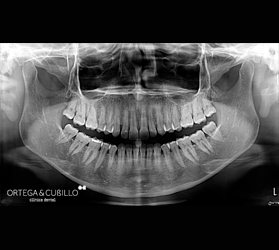

Realizamos ortopantomografías y telerradiografías que son pruebas radiológicas de gran importancia en el tratamiento de ortodoncia e implantología. Asimismo se pueden realizar pequeñas tomografías, radiología de la articulación temporomandibular , senos maxilares y muñeca en este caso para determinar el estado de maduración ósea durante el crecimiento.